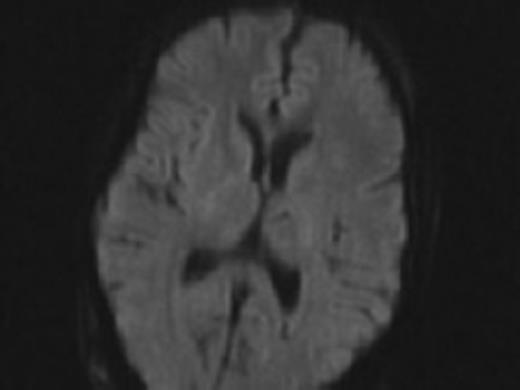

Thereafter, her ventricles diminished in size back to their baselines and her neurological exam slowly improved back to her baseline over the course of 2 months. She had no lesions noted in the opercular regions on her MRI post operatively (Fig. 4).

Difussion MRI of the brain prior to syndrome showing no areas of stroke.